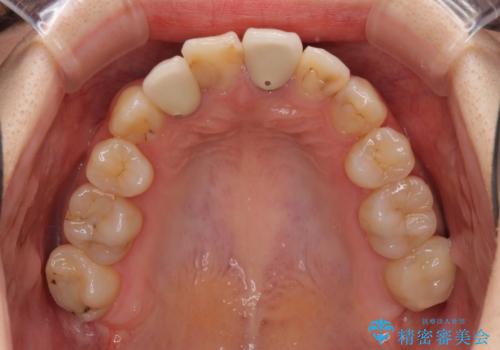

- 奥歯が痛いとのことで来院された患者様です。

上顎親知らず周辺の炎症と、神経組織の失活した歯の炎症による痛みが認められたため、親知らずの抜歯と根管治療を行いました。

根管治療を行った歯はクラウンによる補綴治療が必要となりますが、高校生の頃に行った矯正治療の後戻りも気になるとのことで、補綴治療を行う前に矯正治療を行うこととしました。

後戻りは軽度であり、インビザラインにて歯列を整え、その後にオールセラミッククラウンにて補綴治療を行うこととしました。